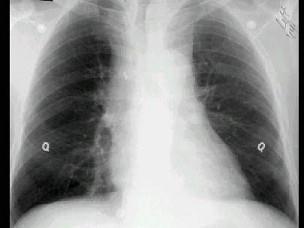

问题 男,26岁,自觉肌无力两周,胸片检查见纵隔增宽,CT检查如图,最可能的诊断为 ( )

选项 A、淋巴瘤侵犯血管 B、下纵隔畸胎瘤 C、胸内甲状腺瘤 D、中纵隔胸腺瘤侵犯血管 E、上纵隔畸胎瘤

答案 D